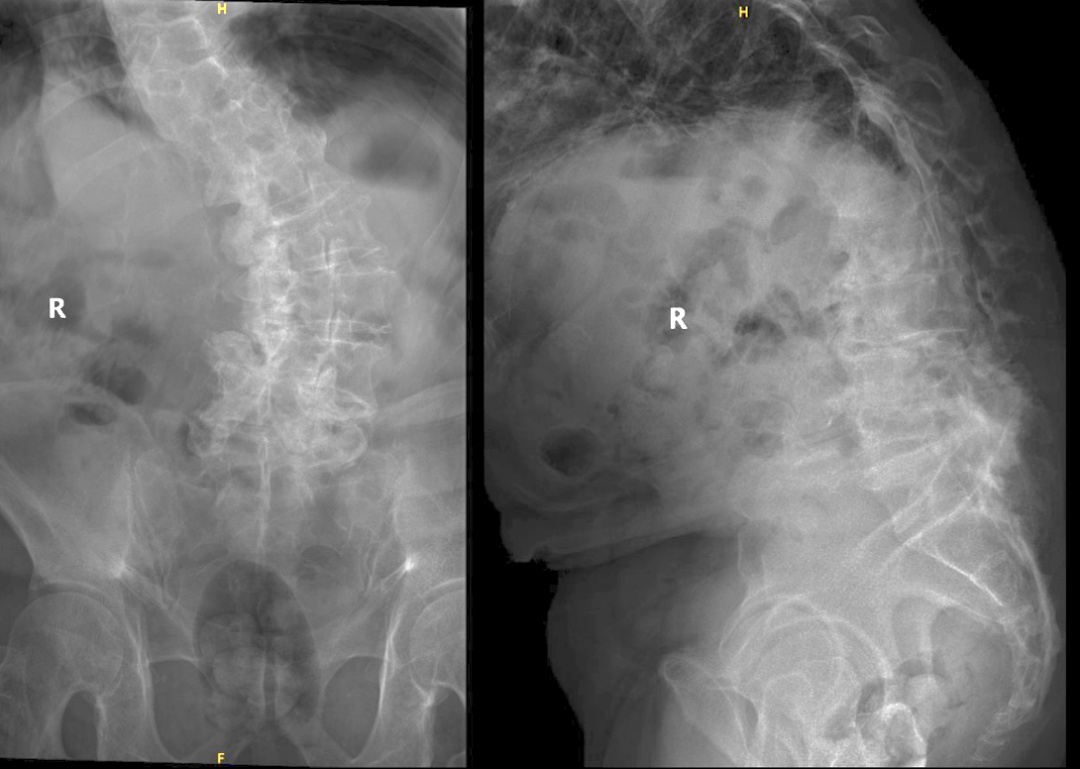

老人X线示严重侧弯及退变

姜教授与团队仔细分析了老先生的影像学资料,发现老先生存在严重的脊柱退变畸形导致的严重神经压迫,严重的退变令患者的骨性结构与正常解剖结构存在很大差异,手术难度高,风险极大!姜教授及团队在术前进行了细致的规划,通过影像学、电生理、症状体征,“三板斧”综合判断手术责任节段,做到精准打击,力求将创伤控制到最小,但又能保证做到神经减压后的效果。正所谓“凡事预则立,不预则废”,在术前做好充分准备,从而将术中风险降到最低,这是姜教授给团队立下的规矩。

一个月后,王先生被收治入院。此时,老人脊柱侧弯及后凸畸形,活动受限,右下肢运动及感觉功能均有明显减退,步行或久站后会出现难以忍受的腿痛症状。姜建元教授带领的手术专家组与呼吸科、心内科和麻醉科等多科室联合会诊,完善相关检查,评估了王老的全身情况后,确定他能承受全麻手术。同时再次与老人和家属沟通,阐明了手术的风险和预后,并得到了患者的理解和全力配合。最终,姜教授和他的团队决定为王先生行“腰椎后路部分椎板切除减压术”,以期解除困扰他已久的病痛。